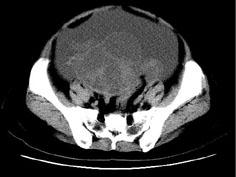

问题 女,27岁,腹胀伴消瘦两个月,CT检查如图所示,应诊断为 ( )

选项 A、卵巢粘液性囊腺瘤 B、卵巢粘液性囊腺癌 C、卵巢浆液性囊腺瘤 D、卵巢浆液性囊腺癌 E、子宫肌瘤

答案 D